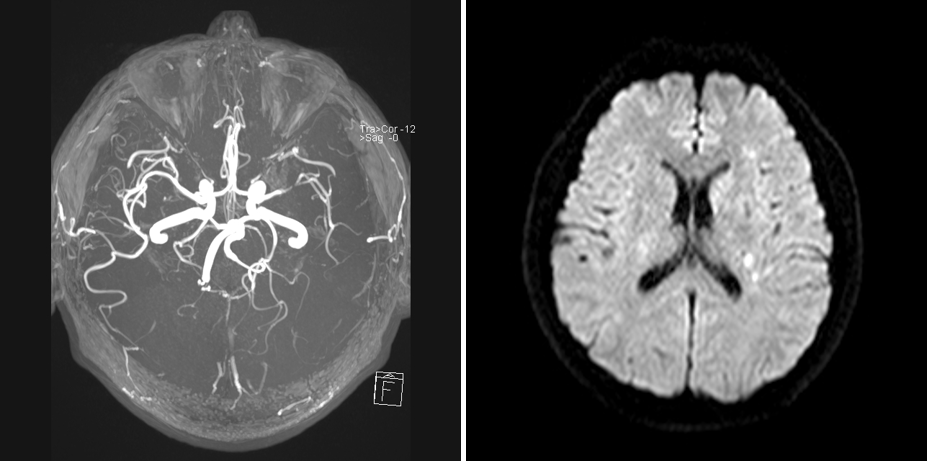

既往病史影像留存

MRA

DWI

重要影像结论:左基底节区、放射冠区脑梗死,左大脑中动脉M1末端狭窄。